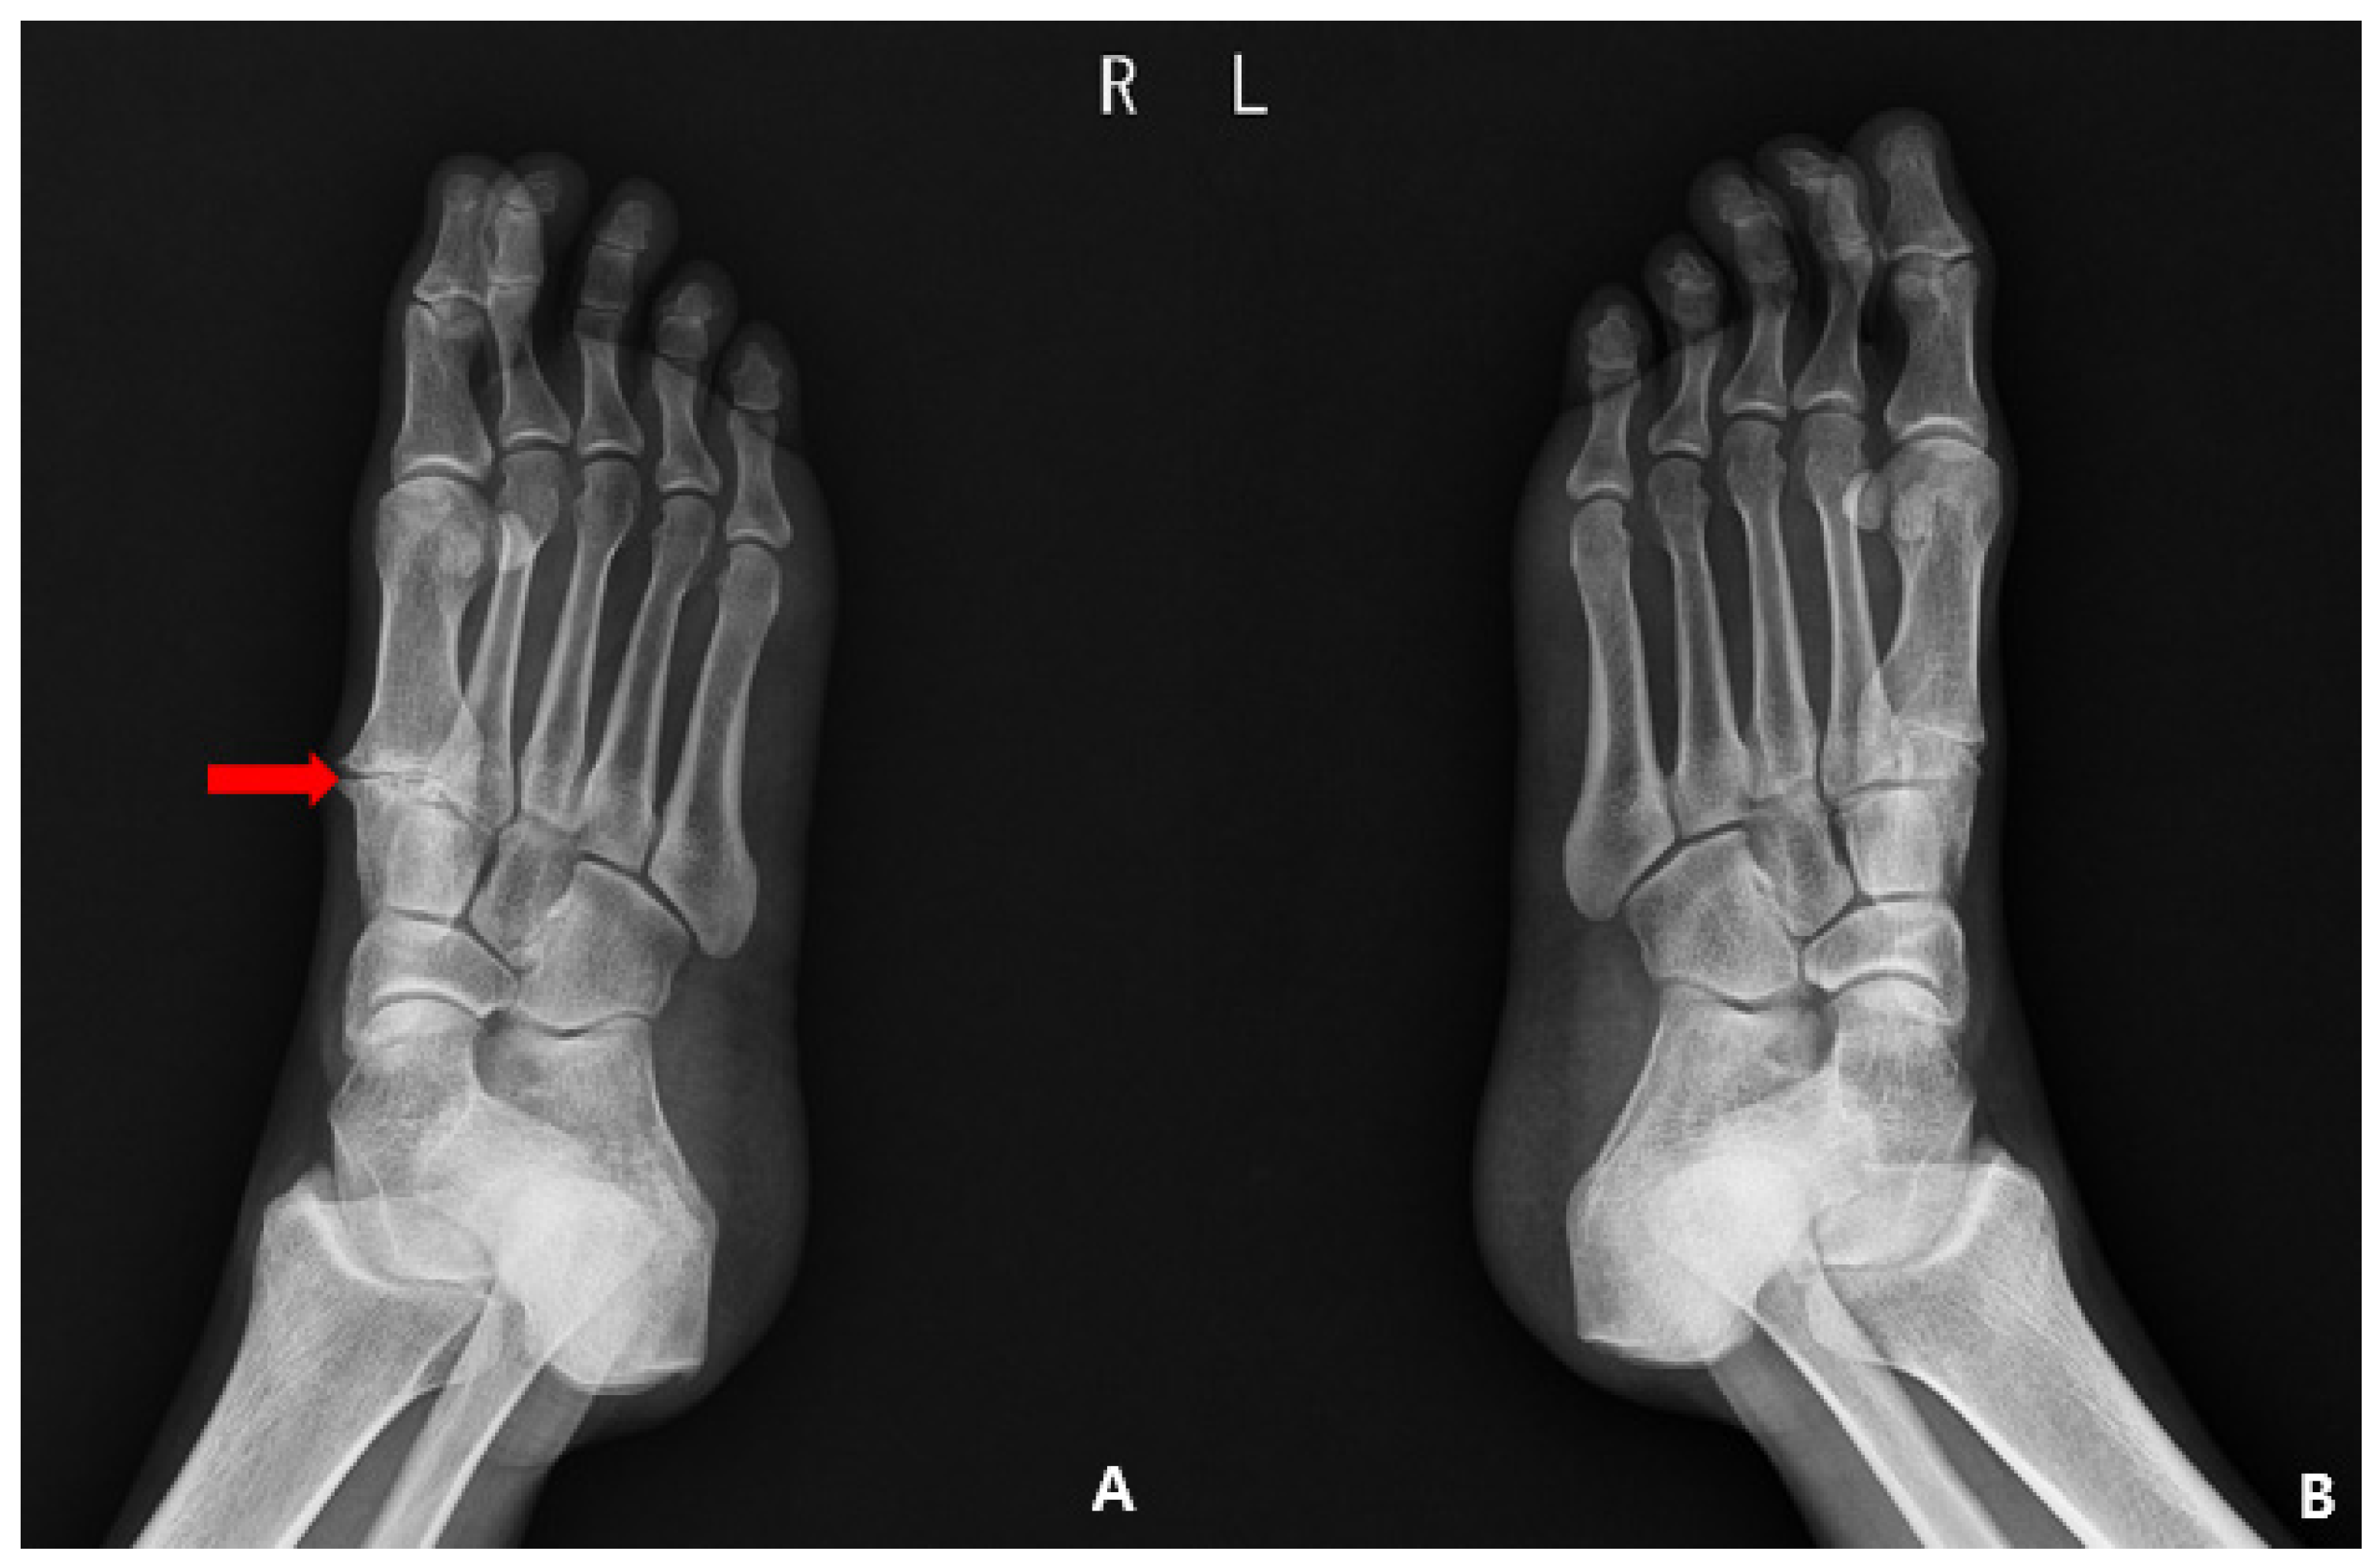

1. Introduction

2. Case Presentation

2.1. Preoperative Evaluation